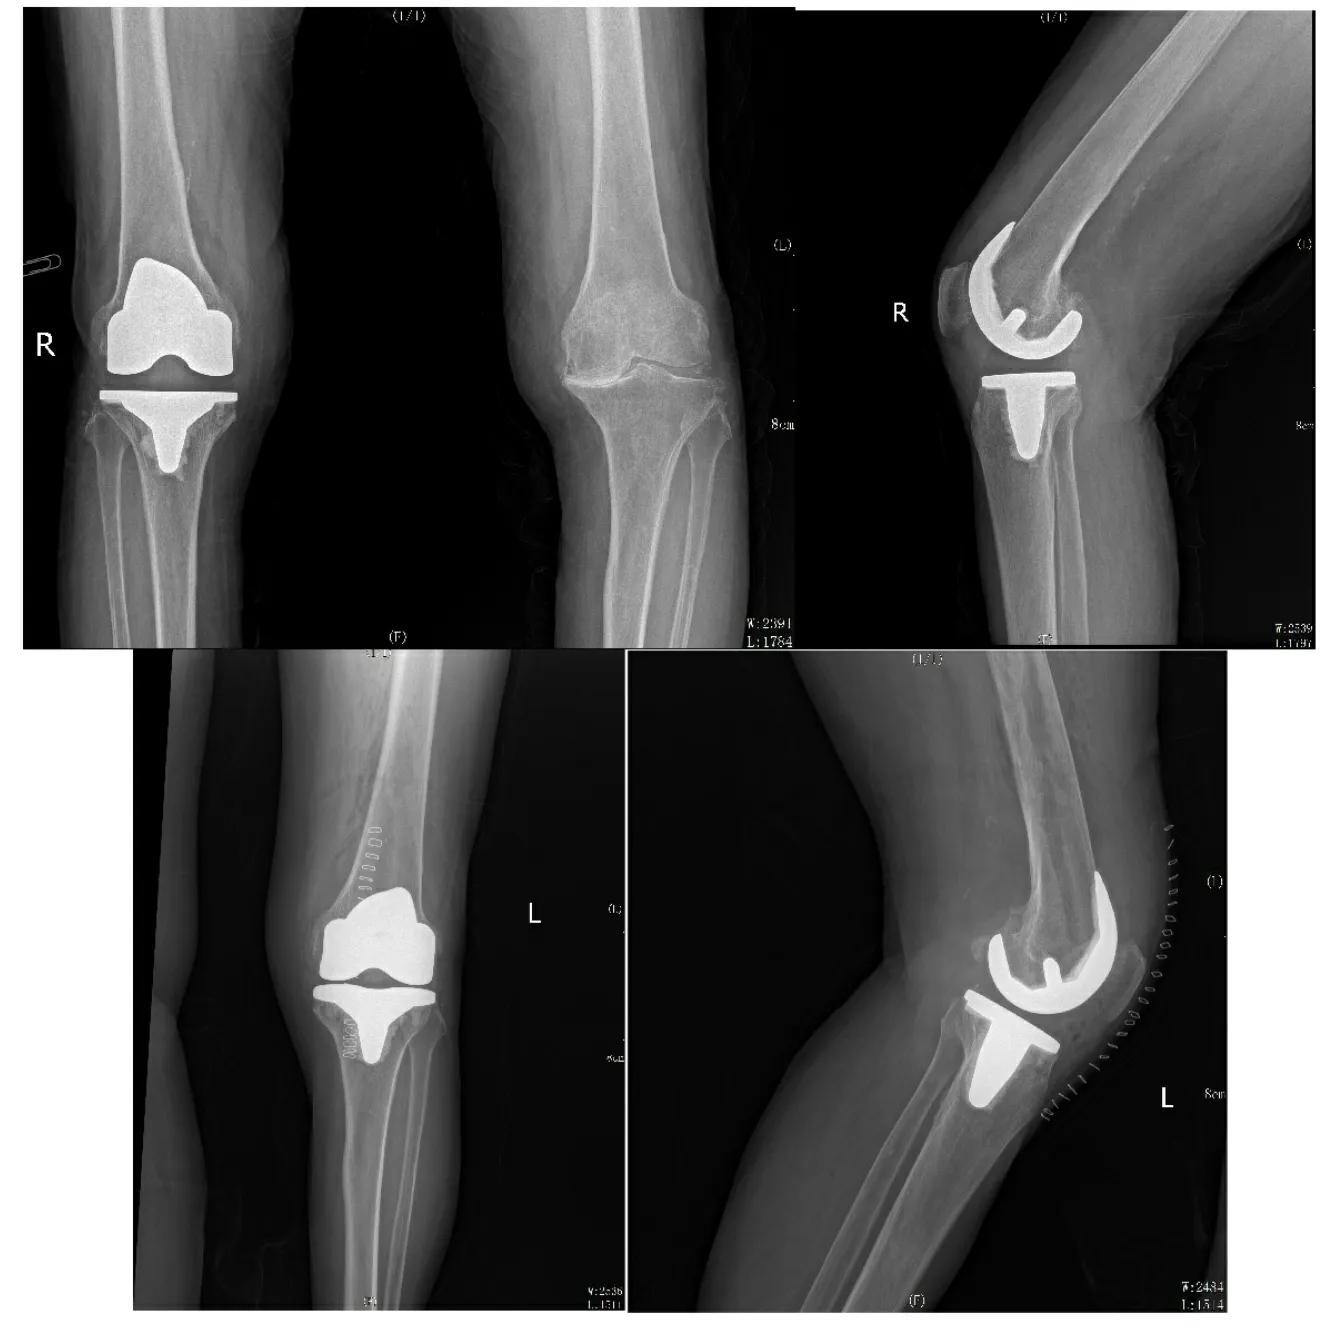

影像学检查

X线片:双侧股骨下端、胫骨内外侧髁边缘硬化增白伴骨赘形成,髌骨边缘及髁间隆突变尖。关节面不光整,关节间隙变窄。关节囊及关节周围软组织未见异常。

术前影像检查

影像学显示:

双膝内翻畸形。

骨质增生硬化,关节间隙明显变窄。

骨磨骨,内侧胫骨平台骨性磨损。

术后影像学检查